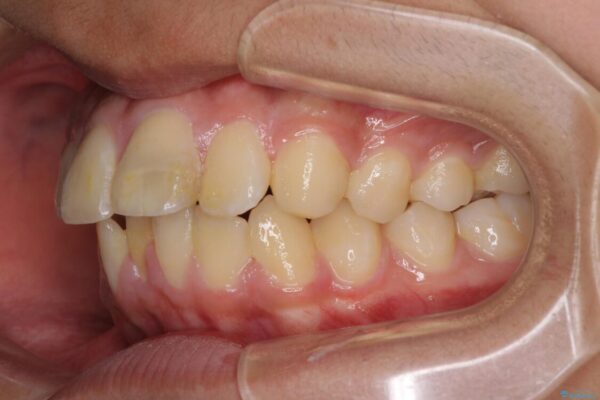

口元の突出感を気にして来院された患者様です。

上下前歯が著しく前突している状態であったので、上下左右の第1小臼歯4本を抜歯し、ワイヤー装置にて矯正治療を行うこととしました。

舌の突出癖により、前突になったと考えられたため、舌のトレーニングをしっかりと行うよう指導しました。

治療前

• 膨らんだ口元 ワイヤー装置での抜歯矯正 治療前画像